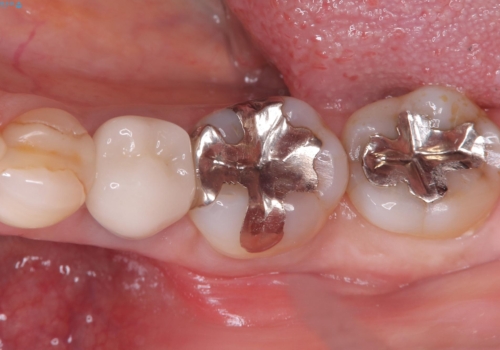

銀歯を白くしたい セラミックインレー

- 銀歯を白くしたいとのことでした。材料の違いを説明し、セラミックインレーでの治療となりました。